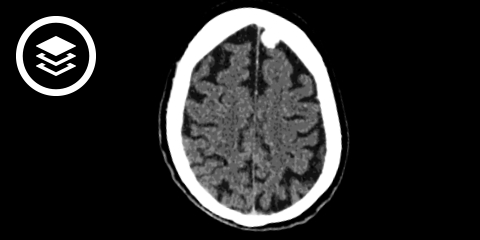

CT-Fallbeispiel

Wegen ihrer Kalkanteile haben Meningeome auch in der Computertomografie ein charakteristisches Aussehen. Sie reichern zu 90 % Kontrastmittel an, 75 % erscheinen hyperdens, 25 % isodens, 25 % sind verkalkt und 10 % haben zystische Anteile. Fast beweisend für das Vorliegen eines Meningeoms sind sonnenstrahlartige Duraausläufer.